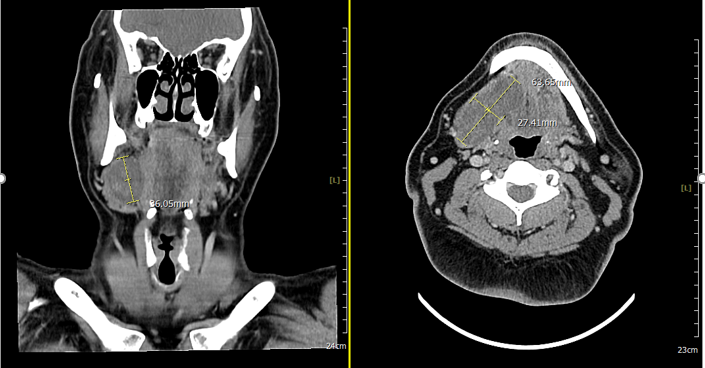

Fine needle aspiration cytology (FNAC) was performed which was found to be non-contributory and did not show any atypical cells. Given the persistent, progressive nature of the swelling, contrast-enhanced CT (CECT) of the neck was done. It showed a well-circumscribed hypodense lesion in the right submandibular space measuring approximately 2.7 × 6.3 × 3.4 cm extending superiorly toward the sublingual region. The lesion abutted the mylohyoid and genioglossus muscles and was seen to be causing compression of the right submandibular gland without any radiological features of infiltration (Figure 1).

Figure 1:- Well-circumscribed cystic/low-attenuation mass in the right submandibular space with superior extension into the ipsilateral sublingual space, causing mass efect on the submandibular gland without definite invasive features.